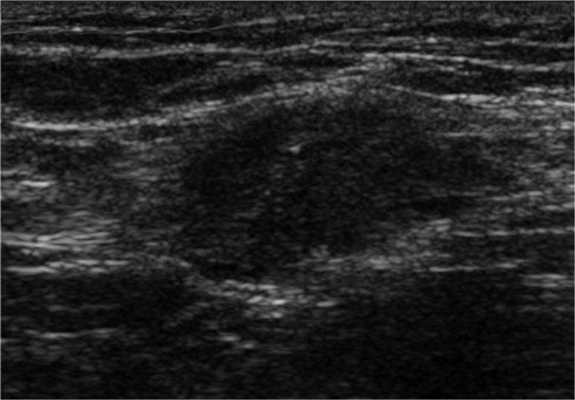

Согласно результатам исследований, эктопическая ткань эндометрия может обнаруживаться в различных нетипичных местах вне полости таза, например, в грудной полости. Брюшная стенка является излюбленной локализацией внетазового эндометриоза, ее поражение обычно связано с кесаревым сечением.

На УЗИ визуализируется солидное гипоэхогенное образование в брюшной стенке, в котором при энергетической допплерографии часто обнаруживается внутренний кровоток. Эти УЗ-признаки не являются специфическими, вследствие чего в дифференциально-диагностический ряд необходимо включать широкий спектр заболеваний, в т. ч. опухолевого характера (саркома, десмоидная опухоль, метастазы) и неопухолевых поражений (гранулема шва, грыжа, гематома или абсцесс). Тем не менее, эндометриоз брюшной стенки в первую очередь необходимо предполагать у пациенток с объемными образованиями данной локализации вблизи шва после кесарева сечения

КТ- и МР-признаки эндометриоза брюшной стенки не являются специфичными: и при КТ, и при МРТ обнаруживается солидное образование в брюшной стенке, накапливающее контраст.